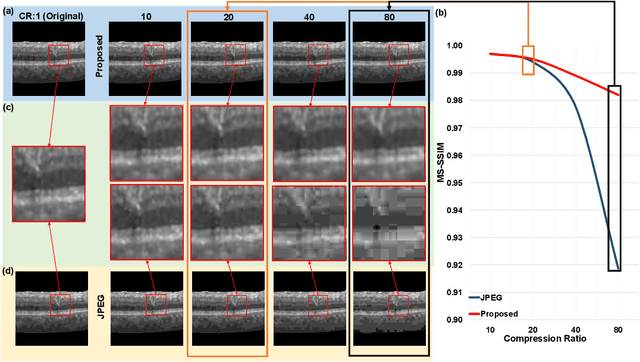

Abstract:We customize an end-to-end image compression framework for retina OCT images based on deep convolutional neural networks (CNNs). The customized compression scheme consists of three parts: data Preprocessing, compression CNNs, and reconstruction CNNs. Data preprocessing module reduces the speckle noise of the OCT images and the segments out the region of interest. We added customized skip connections between the compression CNNs and the reconstruction CNNs to reserve the detail information and trained the two nets together with the semantic segmented image patches from data preprocessing module. To train the two networks sensitive to both low frequency information and high frequency information, we adopted an objective function with two parts: A PatchGAN discriminator to judge the high frequency information and a differentiable MS-SSIM penalty to evaluate the low frequency information. The proposed framework was trained and evaluated on a publicly available OCT dataset. The evaluation showed above 99% similarity in terms of multi-scale structural similarity (MS-SSIM) when the compression ratio is as high as 40. Furthermore, the reconstructed images of compression ratio 80 from the proposed framework even have better quality than that of compression ratio 20 from JPEG by visual comparison. The testing result outperforms JPEG in term of both of MS-SSIM and visualization, which is more obvious as the increase of compression ratio. Our preliminary result indicates the huge potential of deep neural networks on customized medical image compression.